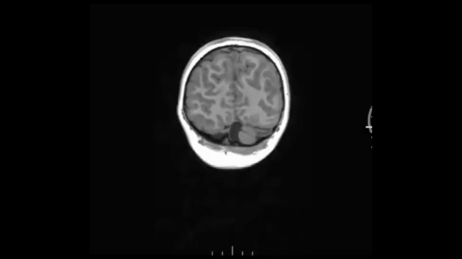

接着,容积解剖成像序列T1W MP – RAGE。等体素扫描,三方面重建轴、矢和冠状面自动重建。

并未见到显著异常。 癫痫三大利器:容积T2 FLAIR、容积T1以及高分辨COR T2W。